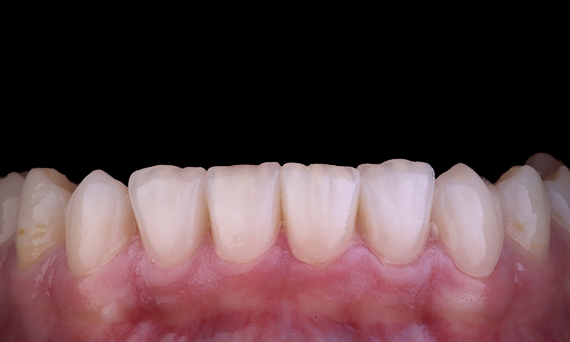

When considering the replacement of a maxillary central incisor with an implant-borne fixed dental prosthesis, case selection, planning and the meticulous application of treatment methods are the keys to success. Immediate implant placement and immediate restoration may minimise tissue loss and result in a highly aesthetic outcome. Implant placement with a fully-guided approach can improve the accuracy of placement, and the placement of the final abutment or restoration at the time of implant placement can promote tissue stability.

Dr Alan Yap, Prosthodontist, Sydney, Australia